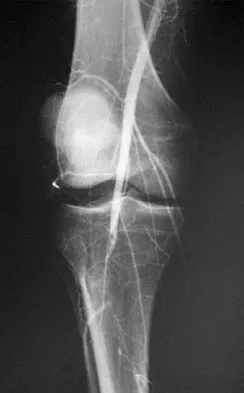

A 58-year-old woman with rheumatoid arthritis and a severe hindfoot valgus deformity now reports recurrent lateral ankle pain. Examination reveals pain over the fibula and sinus tarsi, with a valgus hindfoot that is passively correctable. Despite the use of an ankle-foot orthosis, this is the second time this problem has occurred. Radiographs and a clinical photograph are shown in Figures 28a through 28c. What is the next most appropriate step in treatment?

Explanation

Excessive hindfoot valgus can lead to abutment between the calcaneus and fibula. This valgus force can lead to a stress fracture of the distal fibula. Surgery may be required if an insufficiency fracture recurs despite orthotic management. Of the choices listed, a subtalar arthrodesis is most likely to achieve rebalancing of the foot at the level of the deformity. Stephens HM, Walling AK, Solmen JD, Tankson CJ: Subtalar repositional arthrodesis for adult acquired flatfoot. Clin Orthop 1999;365:69-73